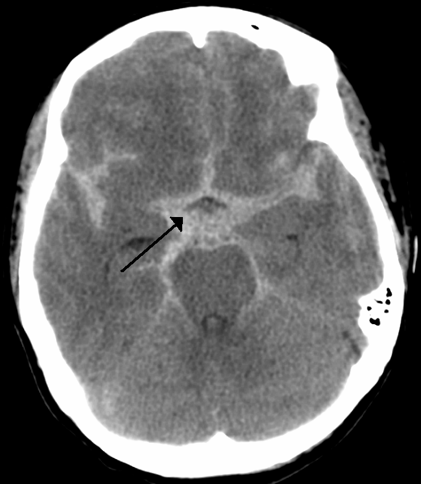

What is this? Where is the blood accumulated?

subarachnoid hemorrhage

subarachnoid space

What vessel(s) is/are the most likely cause of a subarachnoid hemorrhage?

circle of willis vessels